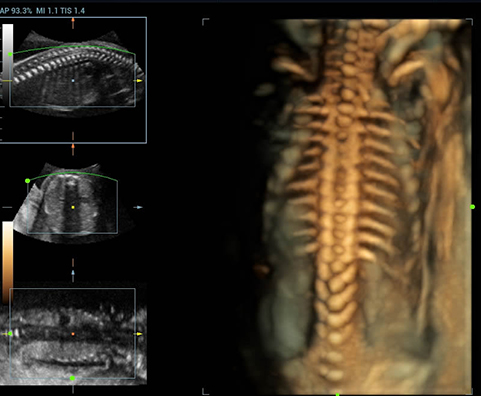

Sejak didirikan, Mindray terus mencari cara baru untuk meningkatkan keandalan diagnostik. Didukung Teknologi ZONE Sonography? terkini, platform ZST+ baru Resona 7 meningkatkan kualitas gambar ultrasound melalui pengambilan zona dan pemrosesan data saluran.

Selain kualitas gambar premium, Resona 7 juga meningkatkan kemampuan penelitian klinis dengan V Flow revolusioner untuk evaluasi hemodinamika vaskular, serta pengambilan penampang tercanggih dari rangkaian data 3D untuk diagnosis CNS pada janin. Kombinasi pengoperasian multisentuh berbasis gerakan yang paling intuitif dengan semua fitur klinis penting membuat Resona 7 menjadi gebrakan baru dalam inovasi ultrasound.